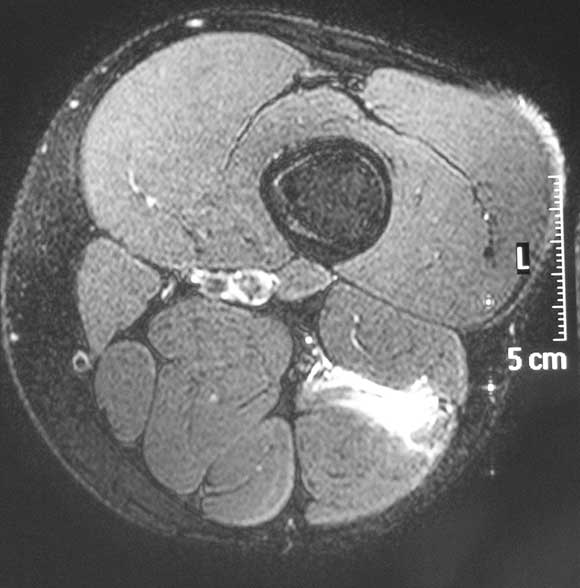

2 Magnetic resonance image

Fat-suppressed T2-weighted axial magnetic resonance image showing high-signal-intensity strain of hamstring muscle (long head of biceps femoris).